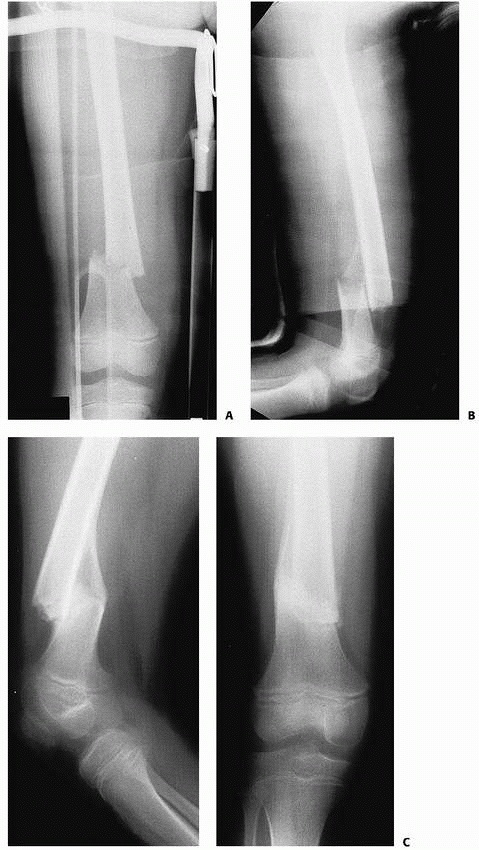

![]() |

|

FIGURE 22-20 AP (A) and lateral (B)

x-rays a low-energy short oblique fracture through a fibrous cortical defect in the distal femur; this type of fracture is not unusual. The surgeon judged that there was enough distance between the fracture site and the growth plate to allow external fixation. AP (C) and lateral (D) x-rays 3 weeks after external fixation shows early callus and good alignment. The external fixation was removed shortly after this x-ray and the child was placed in a long leg cast, with weight bearing as tolerated. |